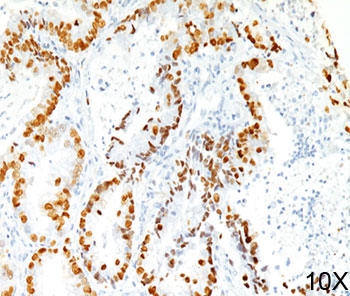

TTF-1 Antibody Clone 8G7G3/1 immunohistochemistry of human lung adenocarcinoma tissue. Human lung adenocarcinoma stained using TTF-1 Antibody Clone 8G7G3/1 demonstrates strong nuclear immunoreactivity for Thyroid transcription factor 1 (NKX2-1) in malignant pulmonary epithelial cells. Nuclear staining highlights tumor cells of pulmonary epithelial origin and reflects the well-established use of clone 8G7G3/1 antibody as a diagnostic immunohistochemistry marker for pulmonary adenocarcinoma. TTF-1 expression in tumor cell nuclei assists pathologists in identifying lung adenocarcinoma and distinguishing primary pulmonary carcinoma from metastatic tumors involving the lung.

TTF-1 Antibody Clone 8G7G3/1 immunohistochemistry of human lung adenocarcinoma tissue. Human lung adenocarcinoma stained using TTF-1 Antibody Clone 8G7G3/1 shows strong nuclear staining for Thyroid transcription factor 1 (NKX2-1) in malignant pulmonary epithelial cells. Nuclear immunoreactivity highlights pulmonary epithelial tumor cells and reflects the diagnostic role of clone 8G7G3/1 antibody in immunohistochemistry panels used for lung adenocarcinoma evaluation. Detection of nuclear NKX2-1 expression supports pulmonary epithelial lineage and helps distinguish primary lung carcinoma from metastatic malignancies.